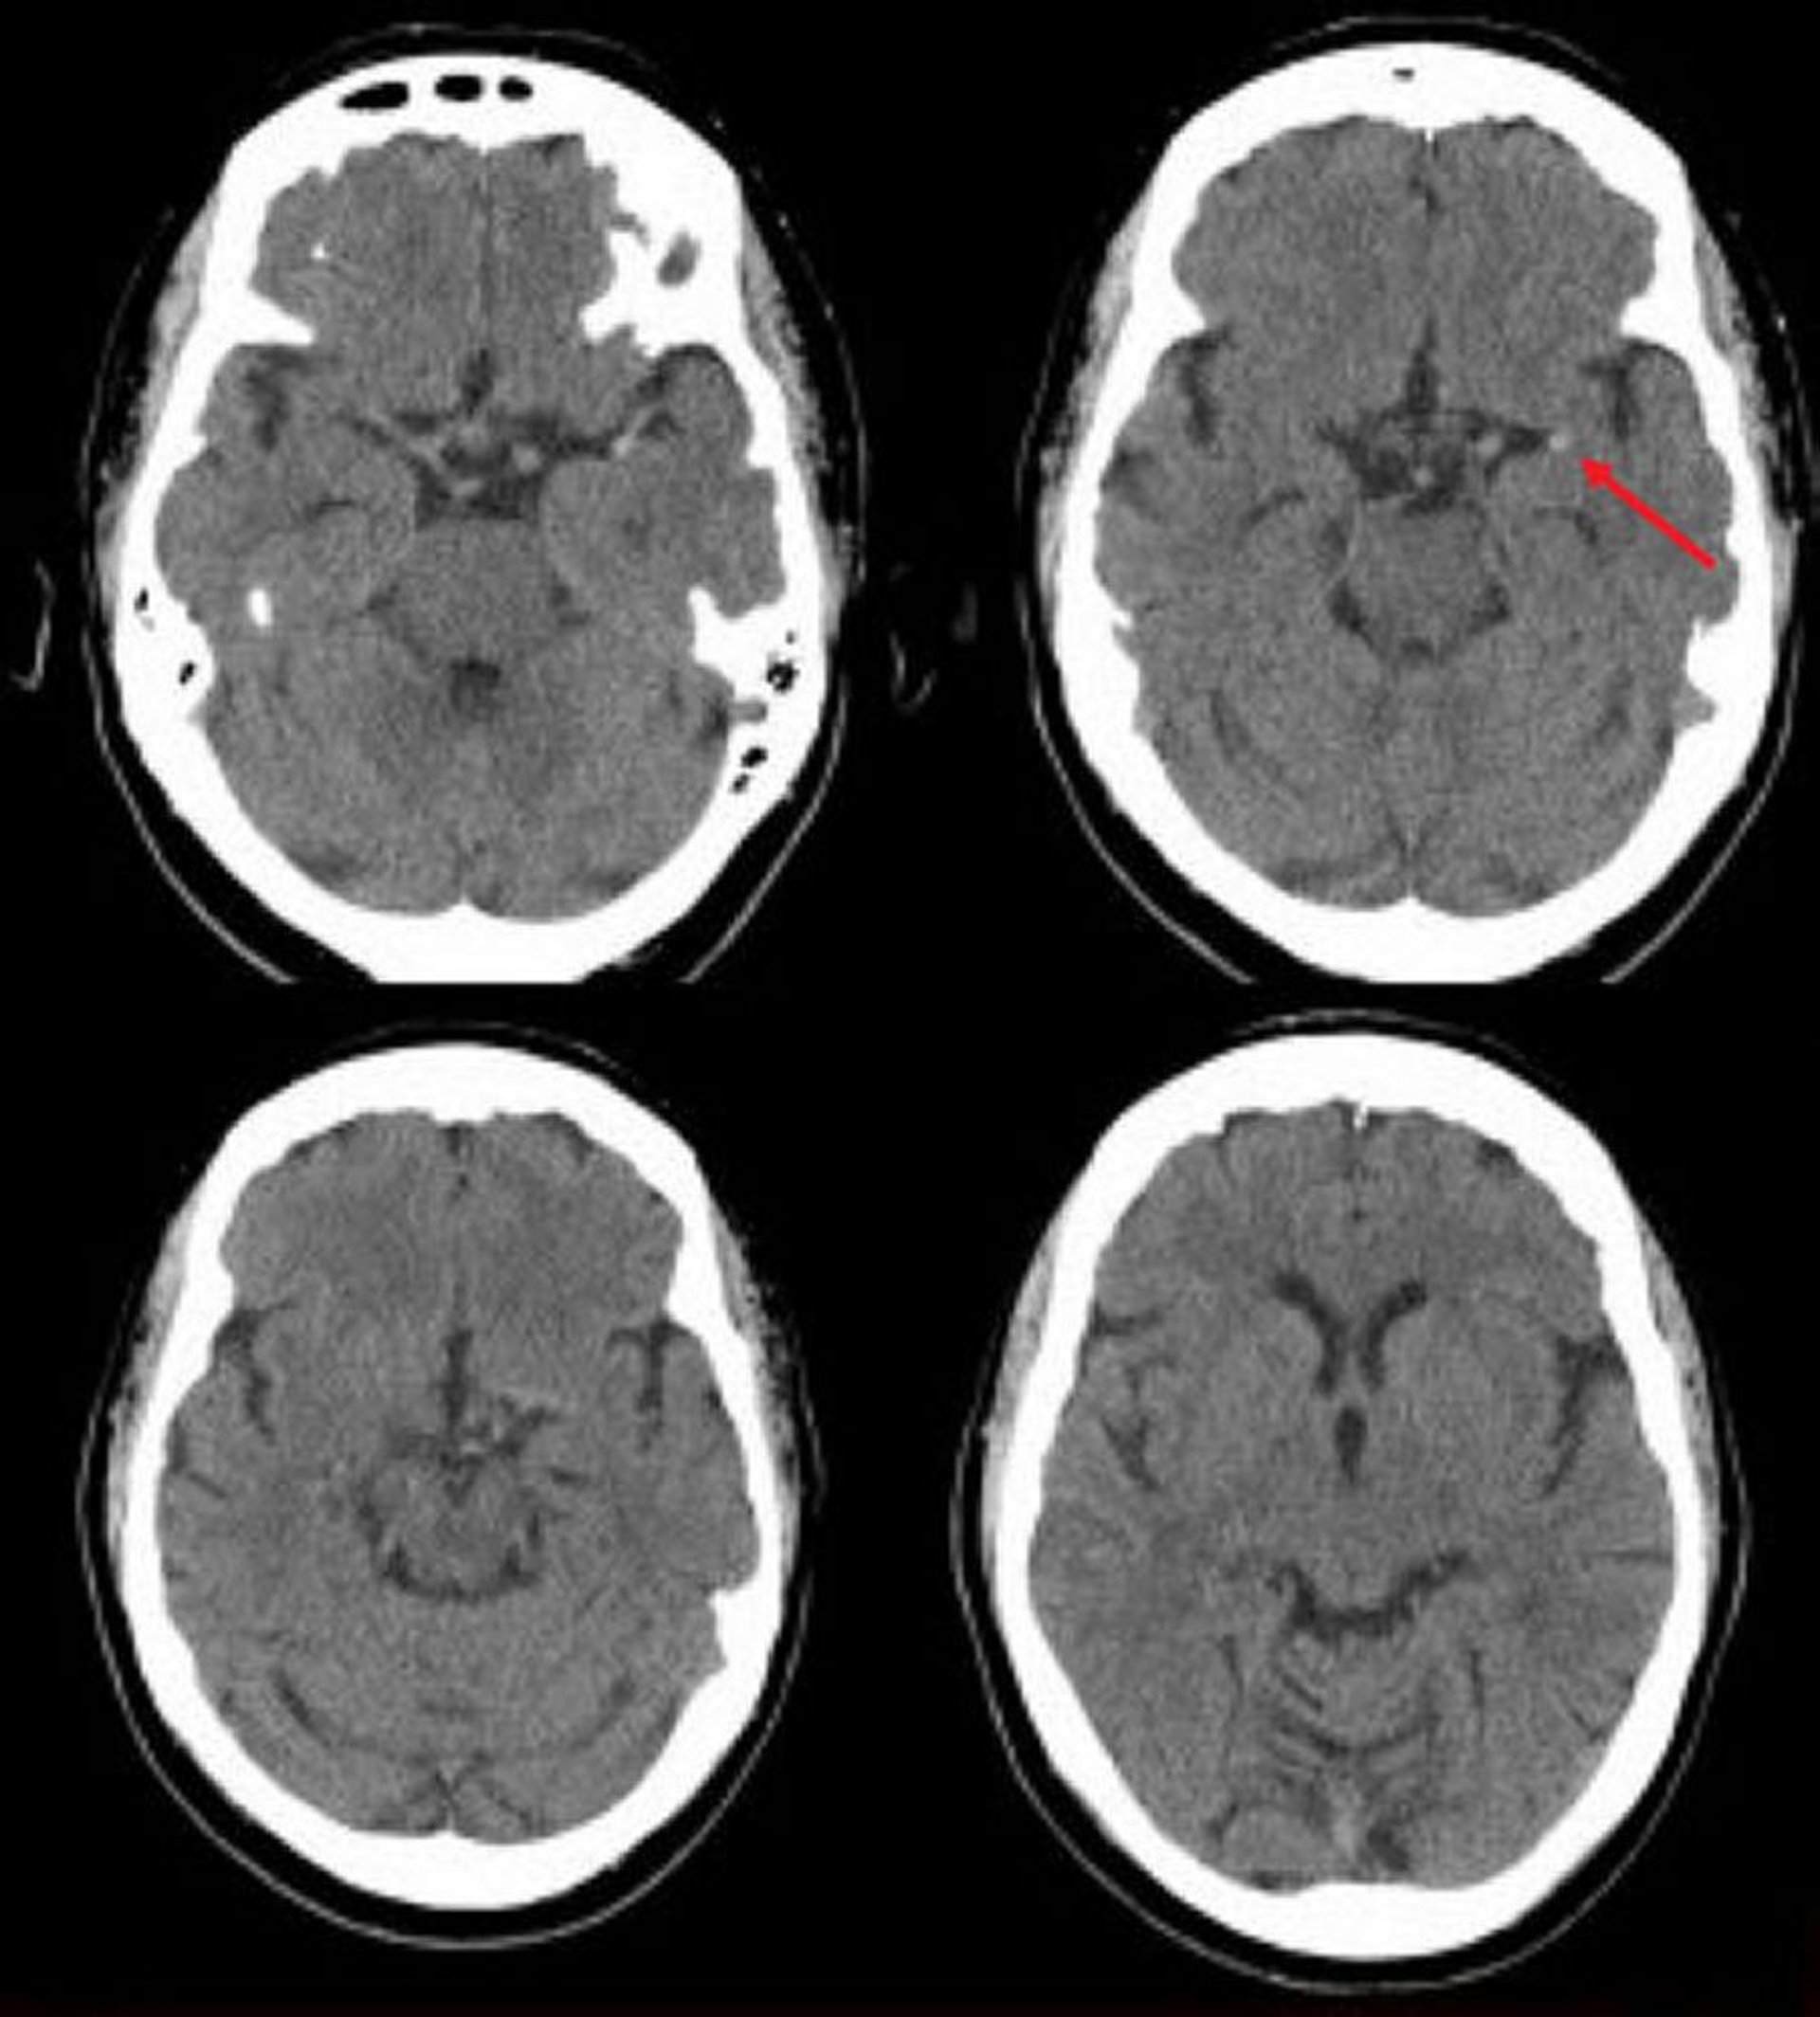

Ischemic Stroke in the Left Middle Cerebral Artery (CT)

This noncontrast head CT scan shows a hyperdense left middle cerebral artery. This finding indicates a focal clot in the left middle cerebral artery (arrow).

Image courtesy of Ji Y. Chong, MD.